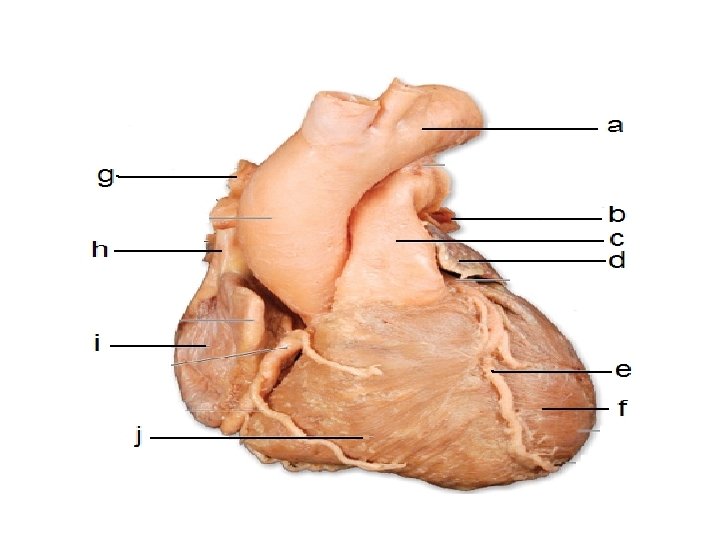

External Structure of the Heart

The Heart Summary Fist sized; found on left side. Consists of cardiac muscle fed by coronary arteries Left side pumps O 2 -rich blood to head and body; Right side pumps O 2 -poor blood to lungs Two upper atria, two lower ventricles Septum separates left and right sides ensuring diffusion gradient • Left ventricle thicker to pump blood all over body • Valves prevent back-flow of blood • • •